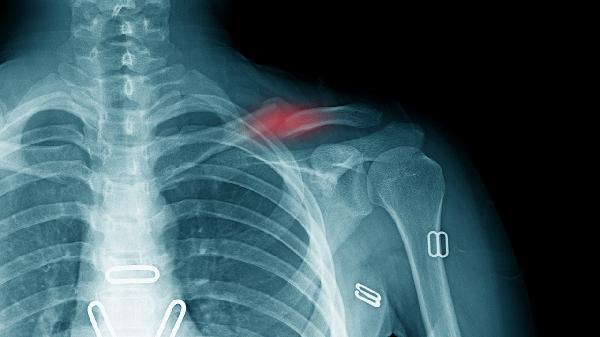

锁骨骨折通常由外伤、运动损伤、骨质疏松、肿瘤转移或先天性骨病等原因引起。锁骨骨折可能与直接暴力撞击、跌倒时手臂外展撑地、骨密度降低、恶性肿瘤侵蚀或成骨不全症等因素有关,常表现为局部肿胀、活动受限、畸形隆起等症状。

锁骨位置表浅,遭受直接暴力撞击如车祸、重物砸伤时易发生骨折。高处坠落或滑倒时手臂外展撑地,外力经肩关节传导至锁骨中段也可导致骨折。此类骨折多为横行或粉碎性,需通过X线检查确诊,急性期需用锁骨带固定4-6周,严重移位时需手术复位内固定。